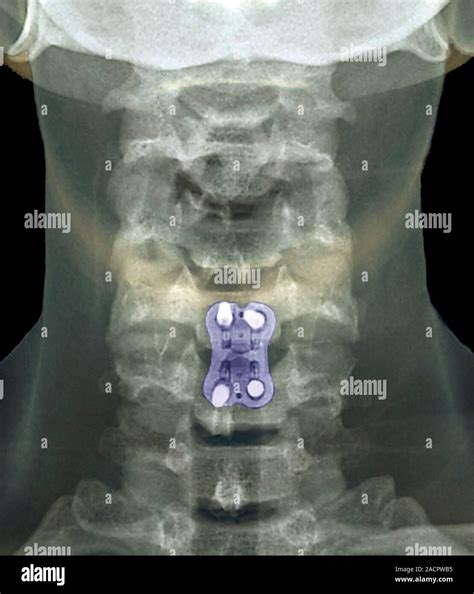

• Imaging Tests: X-rays, MRI, or CT scans to visualize the bones and soft tissues in the neck.

In severe cases where conservative treatments are ineffective, surgery may be considered. Surgical options include:

• Spinal fusion: Joining two or more vertebrae to stabilize the spine